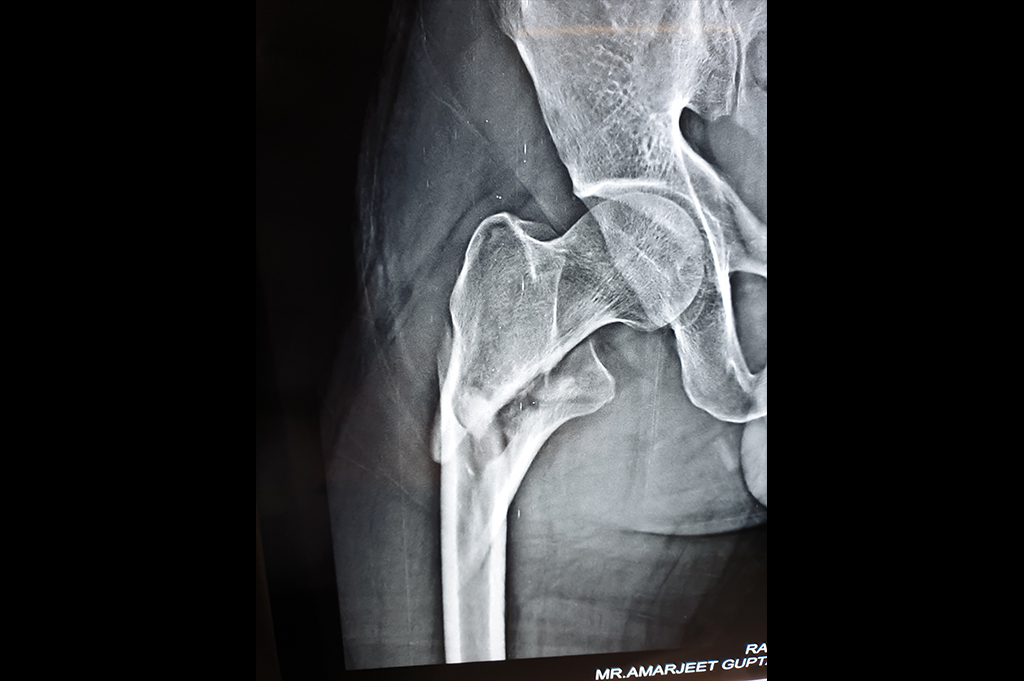

Intertrochanteric Fracture

Neck Femur Fracture